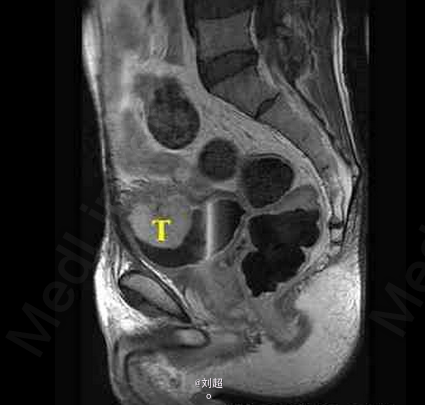

患者尿频、尿急、尿痛,有肉眼可见血尿 辅查MRI,平扫见膀胱侧壁和前上壁呈菜花样突入腔内,T1WI呈低信号,T2WI呈稍高信号,增强后肿块明显强化

膀胱移行细胞癌 处理:手术配合放疗、化疗